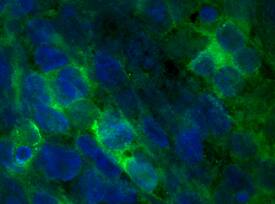

FGF-16 was detected in immersion fixed human induced pluripotent stem (iPS) cells differentiated into cardiomyocytes using Sheep Anti-Human/Mouse FGF-16 Antigen Affinity-purified Polyclonal Antibody (Catalog # AF1212) at 8 µg/mL for 3 hours at room temperature. Cells were stained using the NorthernLights™ 493-conjugated Anti-Sheep IgG Secondary Antibody (green; Catalog # NL012) and counterstained with DAPI (blue). Specific staining was localized to cytoplasm. View our protocol for Fluorescent ICC Staining of Stem Cells on Coverslips.FGF‑16 in Human Heart.

Sample: Immersion fixed human induced pluripotent stem (iPS) cells differentiated into cardiomyocytes